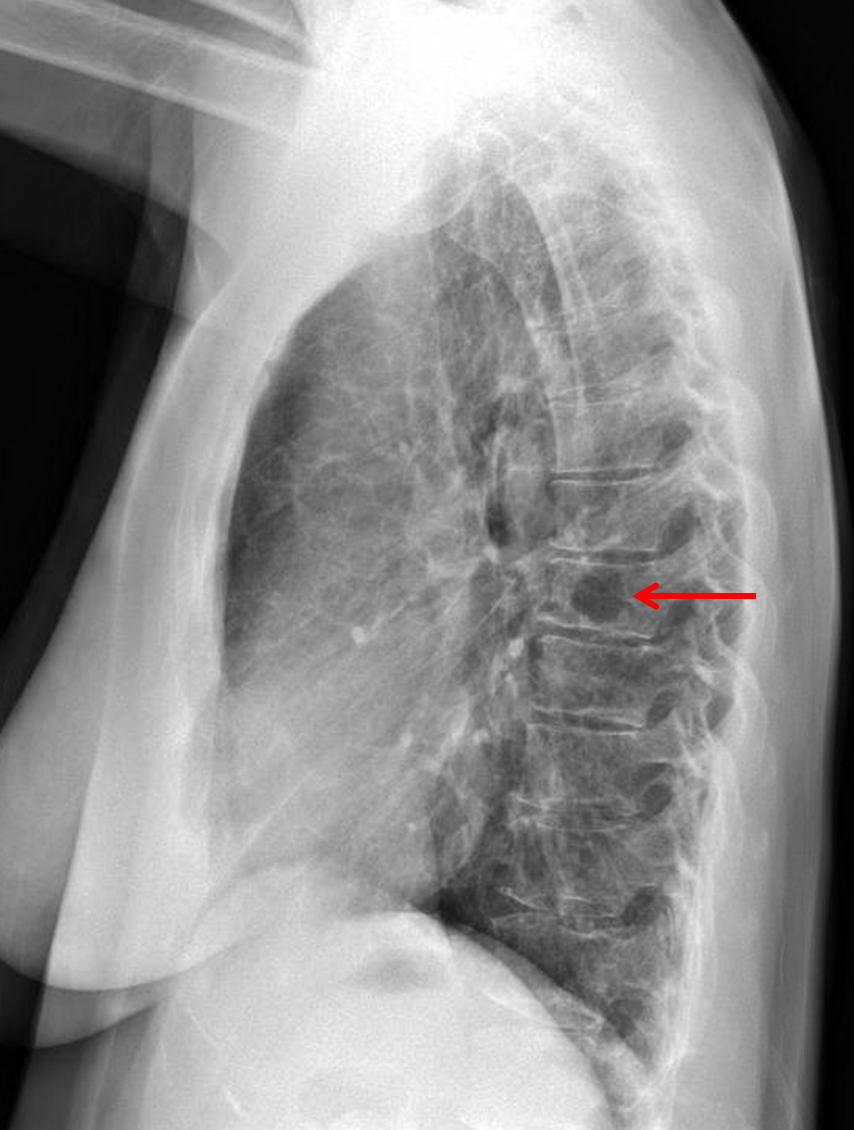

Age: 57

Sex: Female

Indication: Chest pain

Sample ReportLucency projecting over a midthoracic vertebral body on the lateral projection. Consider T-spine MRI with and without contrast for further evaluation.